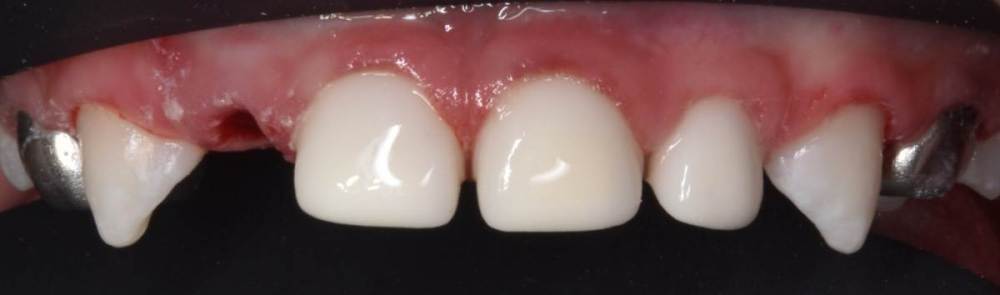

CRAZYDUCK Опубликовано 29 июня, 2022 Автор Поделиться Опубликовано 29 июня, 2022 Герметизация тоже в изоляции . по случаю - герметизация 3.6 лечение кариеса 74 ,75 . 3 1 Ссылка на комментарий